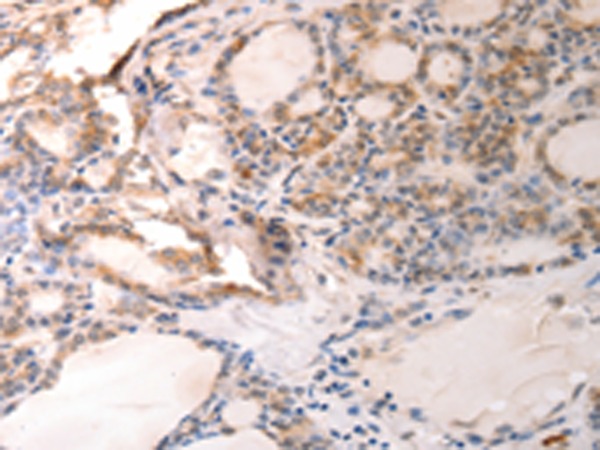

分类: 科研抗体货号: P10717别名: ATG6; VPS30; beclin1应用: WB,IHC反应种属: Human, Mouse, Rat